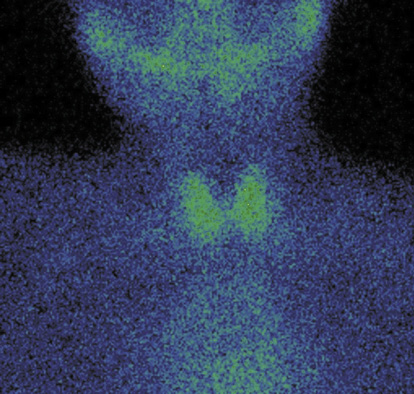

3. Fig. 3. Capture of 99mTc-pertechnetate in the thyroid gland is normal. | |